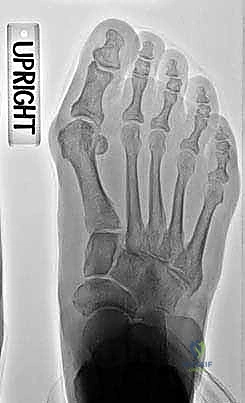

Image

Six week postoperative weight-bearing AP radiograph shows good alignment post-PMOW first metatarsal and distal biplanar chevron bunionectomy.